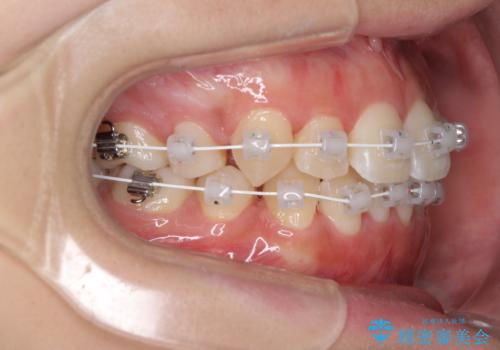

インビザライン単体で治療を行うには叢生が強いと判断されたため、事前にワイヤー装置で抜歯矯正を行い、ある程度改善してからインビザラインにて仕上げていくこととしました。

インビザライン矯正は、患者様の協力が治療結果に最も影響する治療です。

1日22時間、毎日欠かさずにしっかりと装着することが必要条件であるため、自己管理に自信のない方にはお勧めできません。

再度ワイヤー矯正に治療を行うこととなりますと、期間が長くなることはもちろん、治療費用も当初の2倍近くになるため、事前によく検討することが大切です。